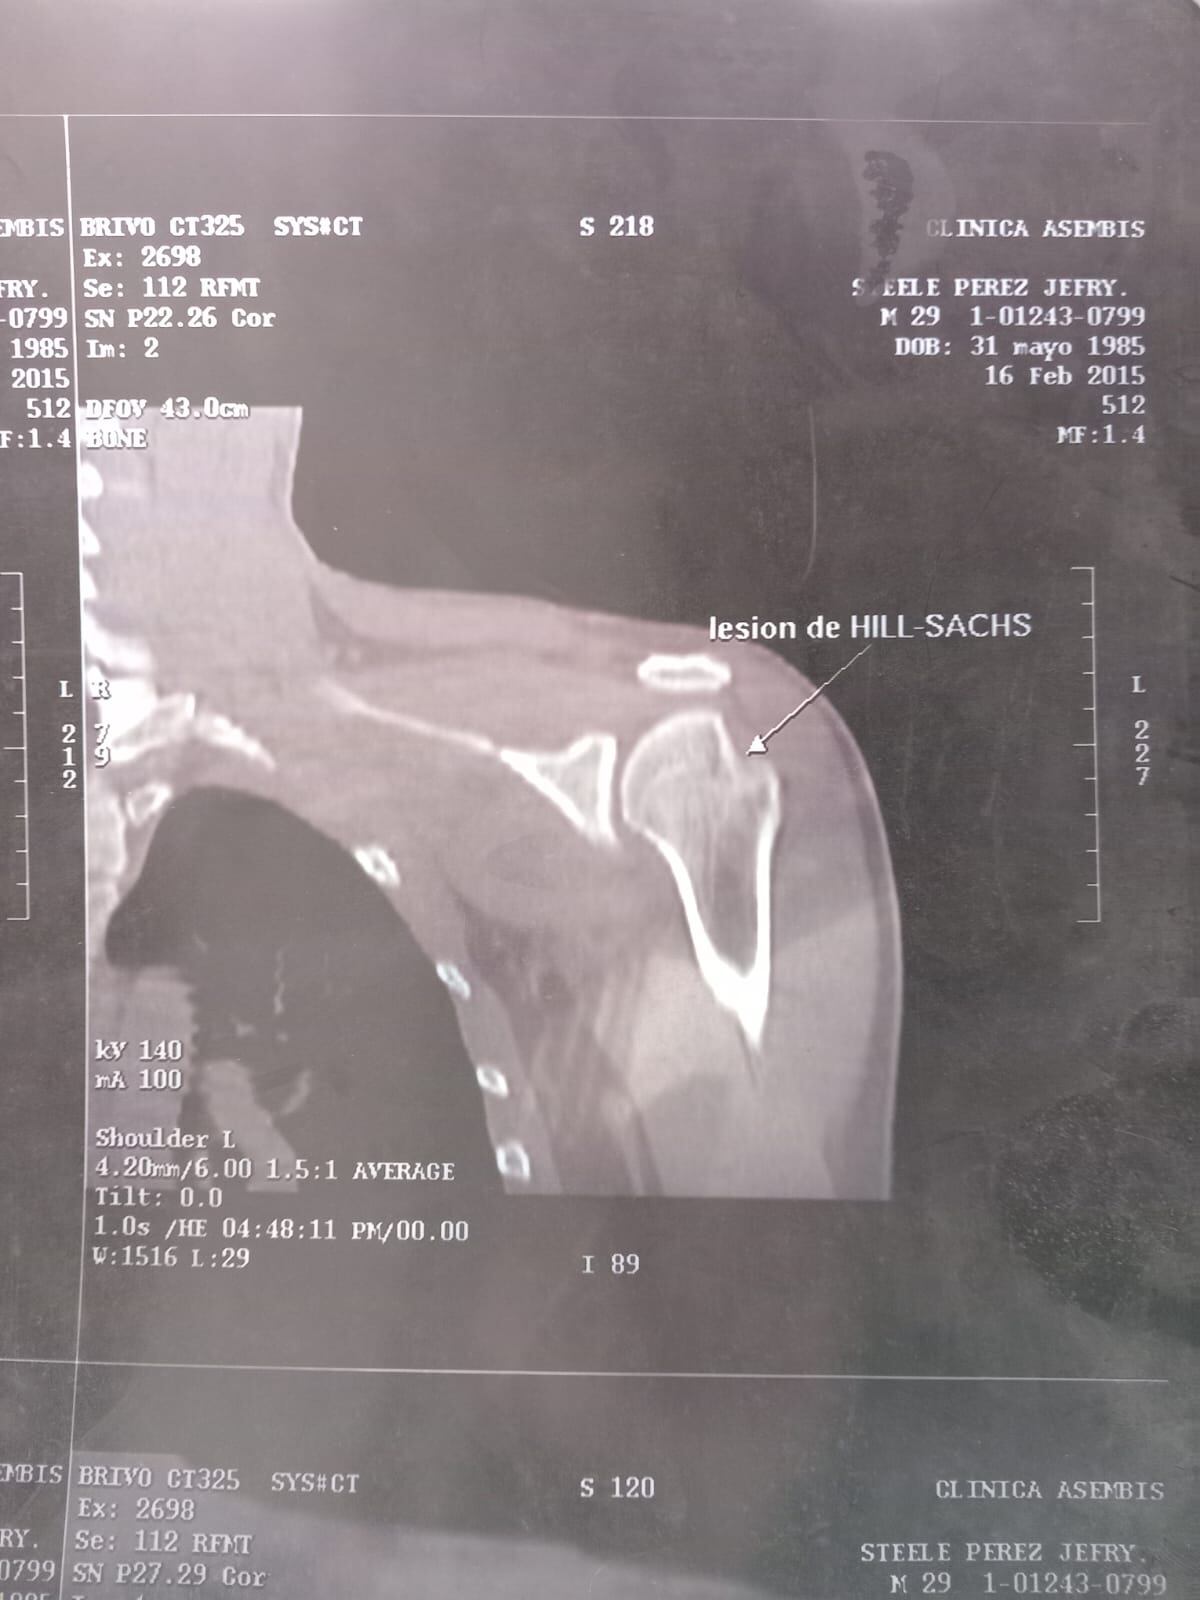

“El 6 de agosto del 2014 en el hospital me mandaron la cita para un TAC, pero me lo progamaron para setiembre del 2015; noté que era mucho tiempo y por eso decidí hacérmelo a nivel privado. En febrero del 2015, lo llevé al hospital, pero me llamaron hasta en el 2018, para valorarme nuevamente”, afirmó.